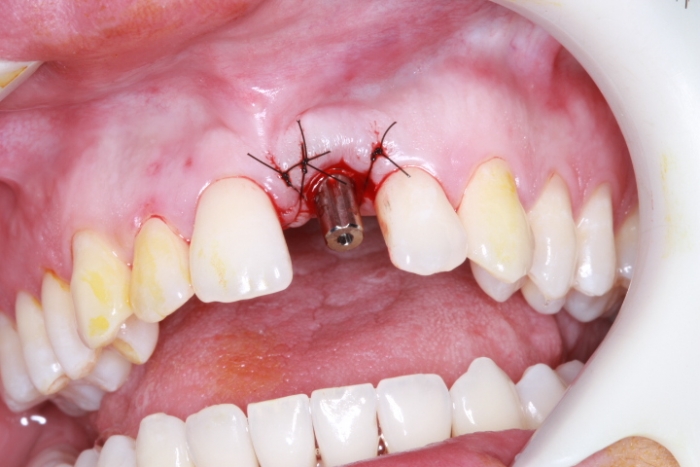

Foto Implante18-05-15